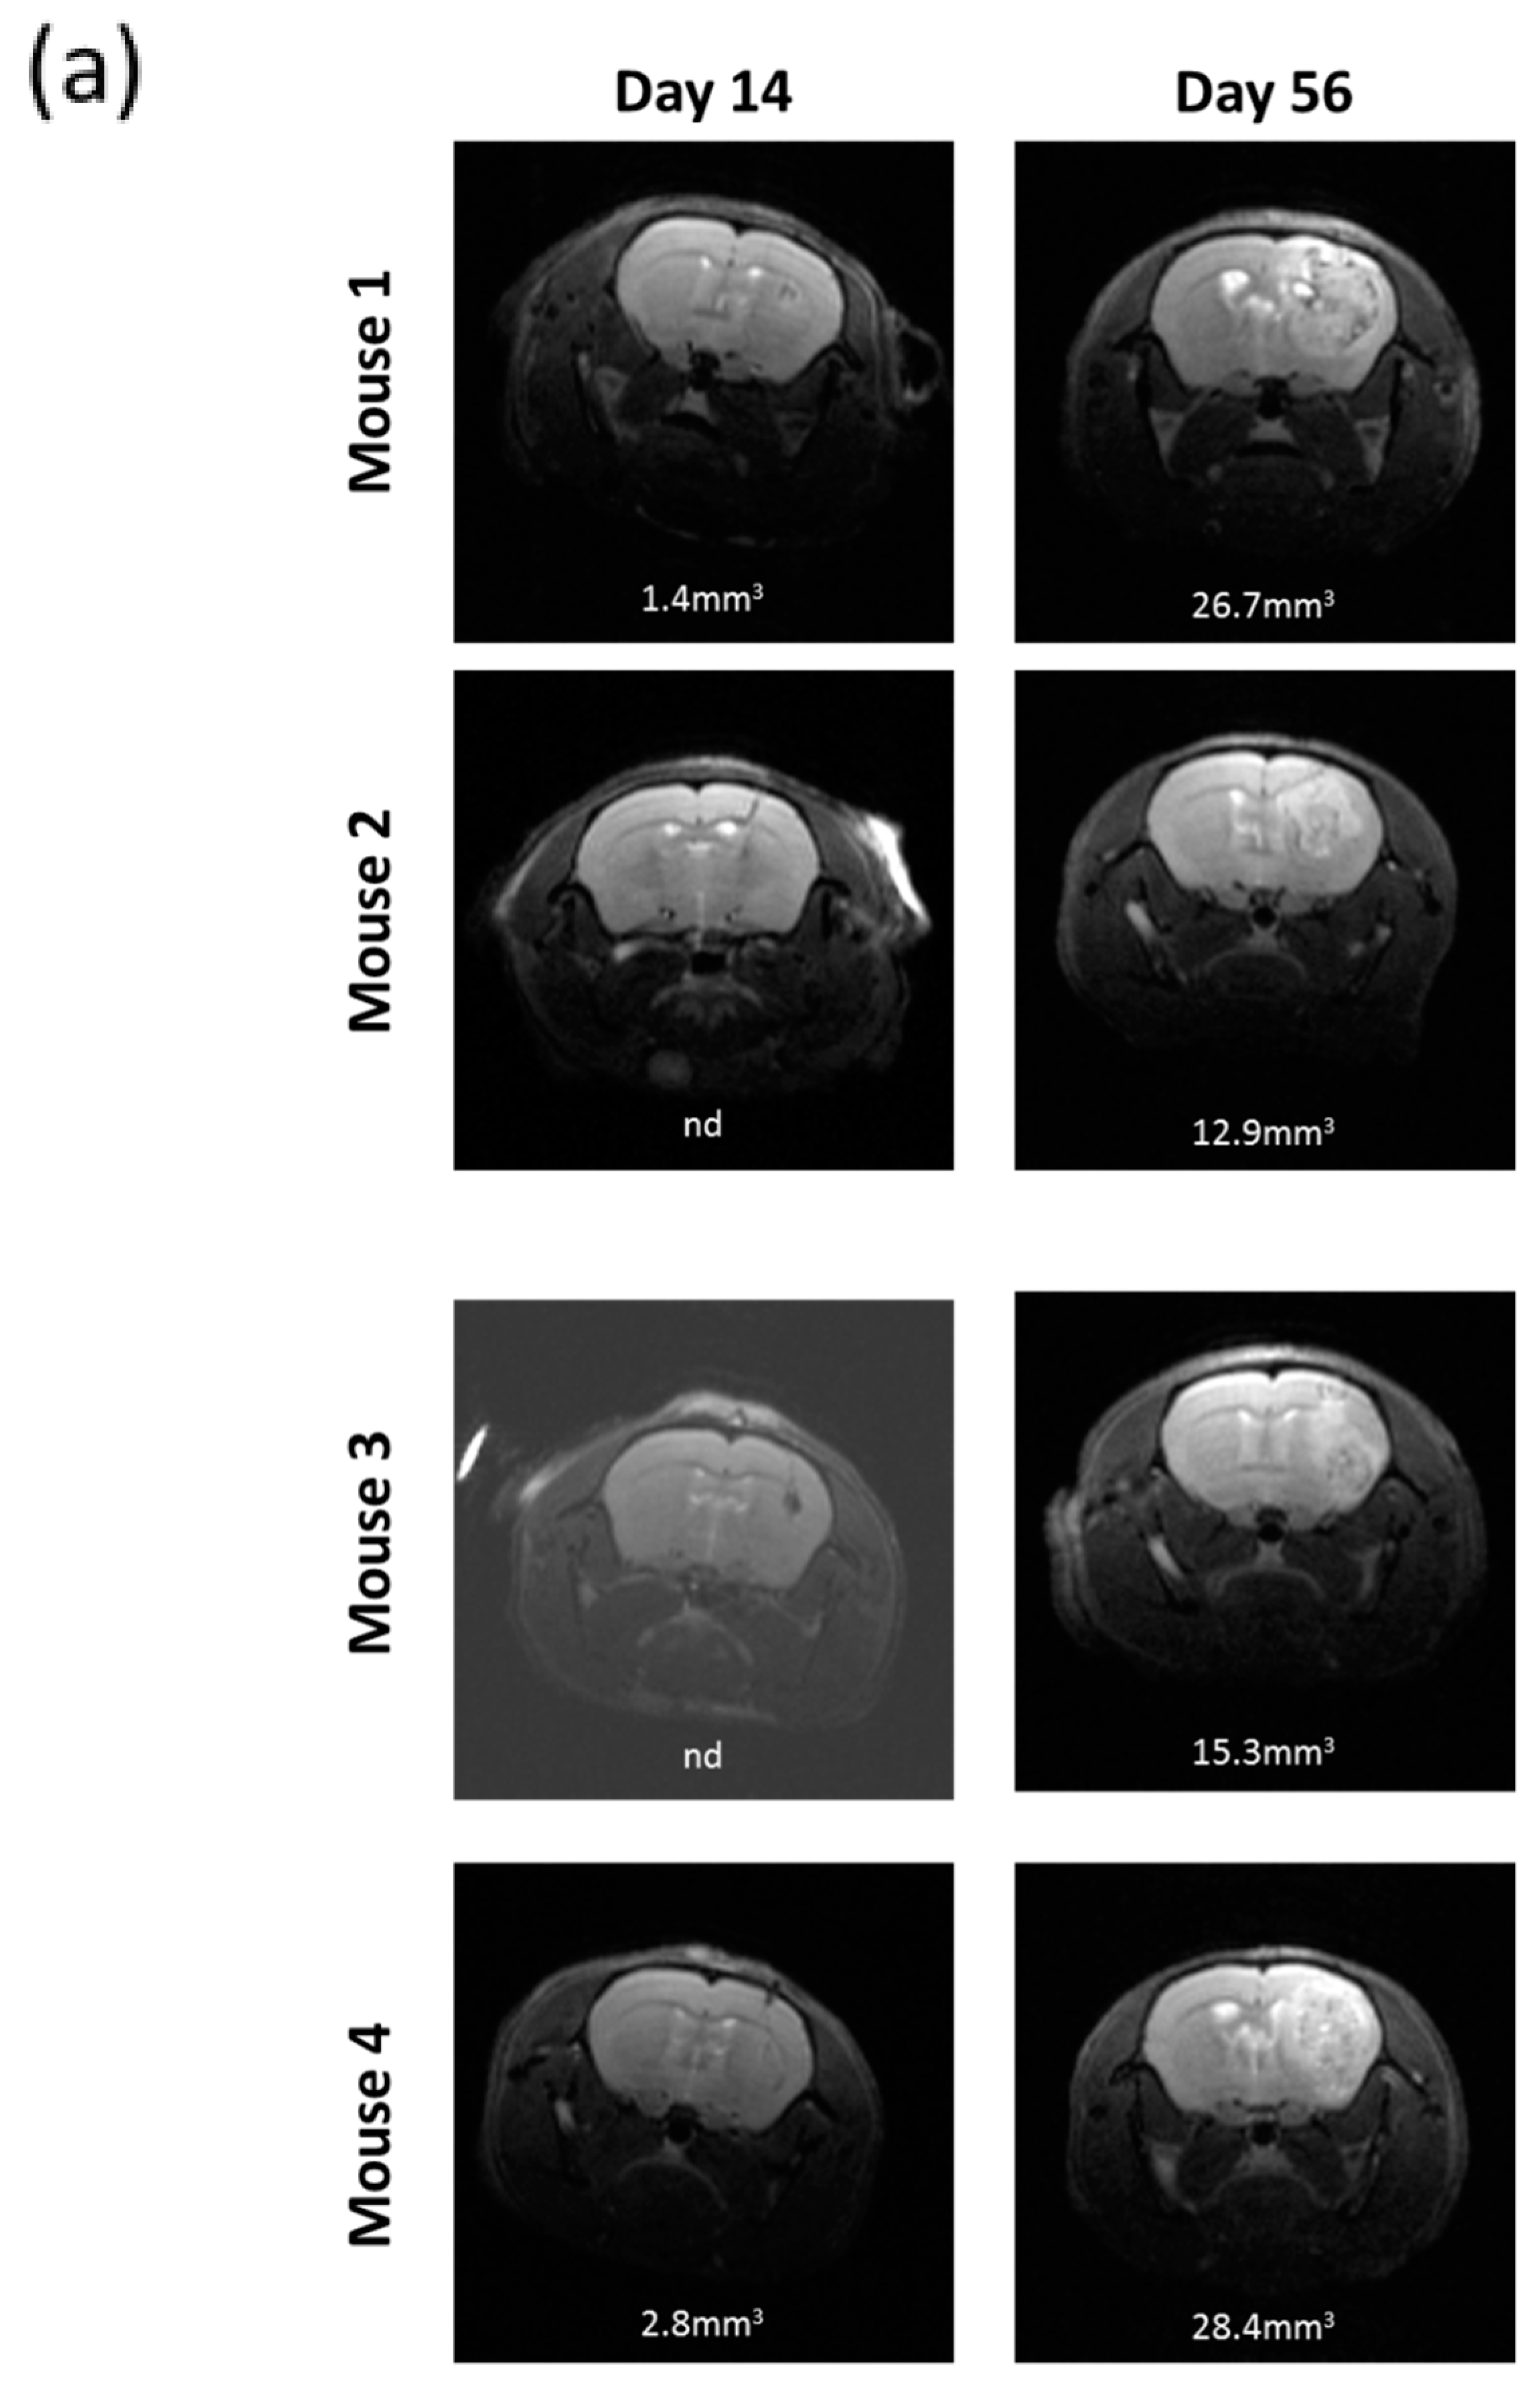

2.7. R2J Cells are Tumorigenic and Cancer Stem Cells

4.10. Magnetic Resonance Imaging